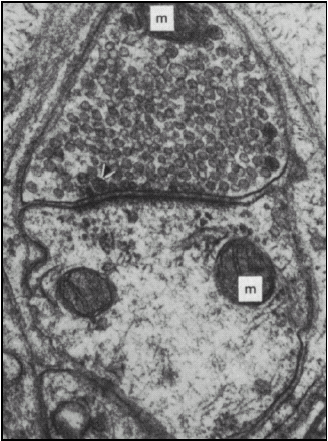

From: Principles of Neural Science, Third edition, Eric R. Kandel, James H. Schwartz, Thomas M. Jessell ©The McGraw-Hill Companies. (m = mitochondria)